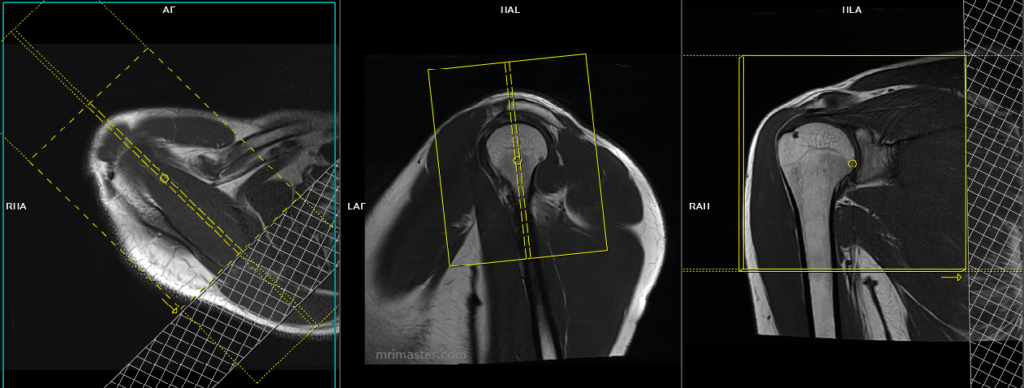

T1 tse coronal 3mm SFOV

Plan the coronal slices on the axial plane and angle the positioning block parallel to the supraspinatus tendon. Do not exceed a 45° angle, as angling more than 45° will result in a change from the coronal plane to the sagittal plane. Verify the positioning block’s alignment in the other two planes. Use an appropriate angle in the sagittal plane, parallel to the humeral head. Ensure that the slices cover the entire shoulder joint, extending from the anterior portion of the coracoid process to two slices posterior to the humeral head. Additionally, consider adding an oblique saturation band over the chest to minimize ghosting artifacts caused by breathing.

Parameters

TR 400-600 | TE 15-25 | SLICE 3 MM | FLIP 130 | PHASE A>P | MATRIX 320X320 | FOV 150-180 | GAP 10% | NEX(AVRAGE) 2 |

T2* medic or PD fat sat coronal 3mm SFOV

Parameters pd fs

TR 3000-4000 | TE 30-40 | SLICE 3 MM | FAT SAT SPAIR | PHASE A>P | MATRIX 320X320 | FOV 150-160 | GAP 10% | NEX(AVRAGE) 2 |

Parameters medic

TR 1000-1200 | TE 30 | SLICE 3 MM | FLIP 40 | PHASE R>L | MATRIX 320X256 | FOV 150-160 | GAP 10% | NEX(AVRAGE) 2 |

T2 stir coronal 3mm SFOV

TR 3000-4000 | TE 110 | FLIP 130 | NEX 2 | SLICE 3MM | MATRIX 320X256 | FOV 150-160 | PHASE H>F | GAP 10% | TI 130 |